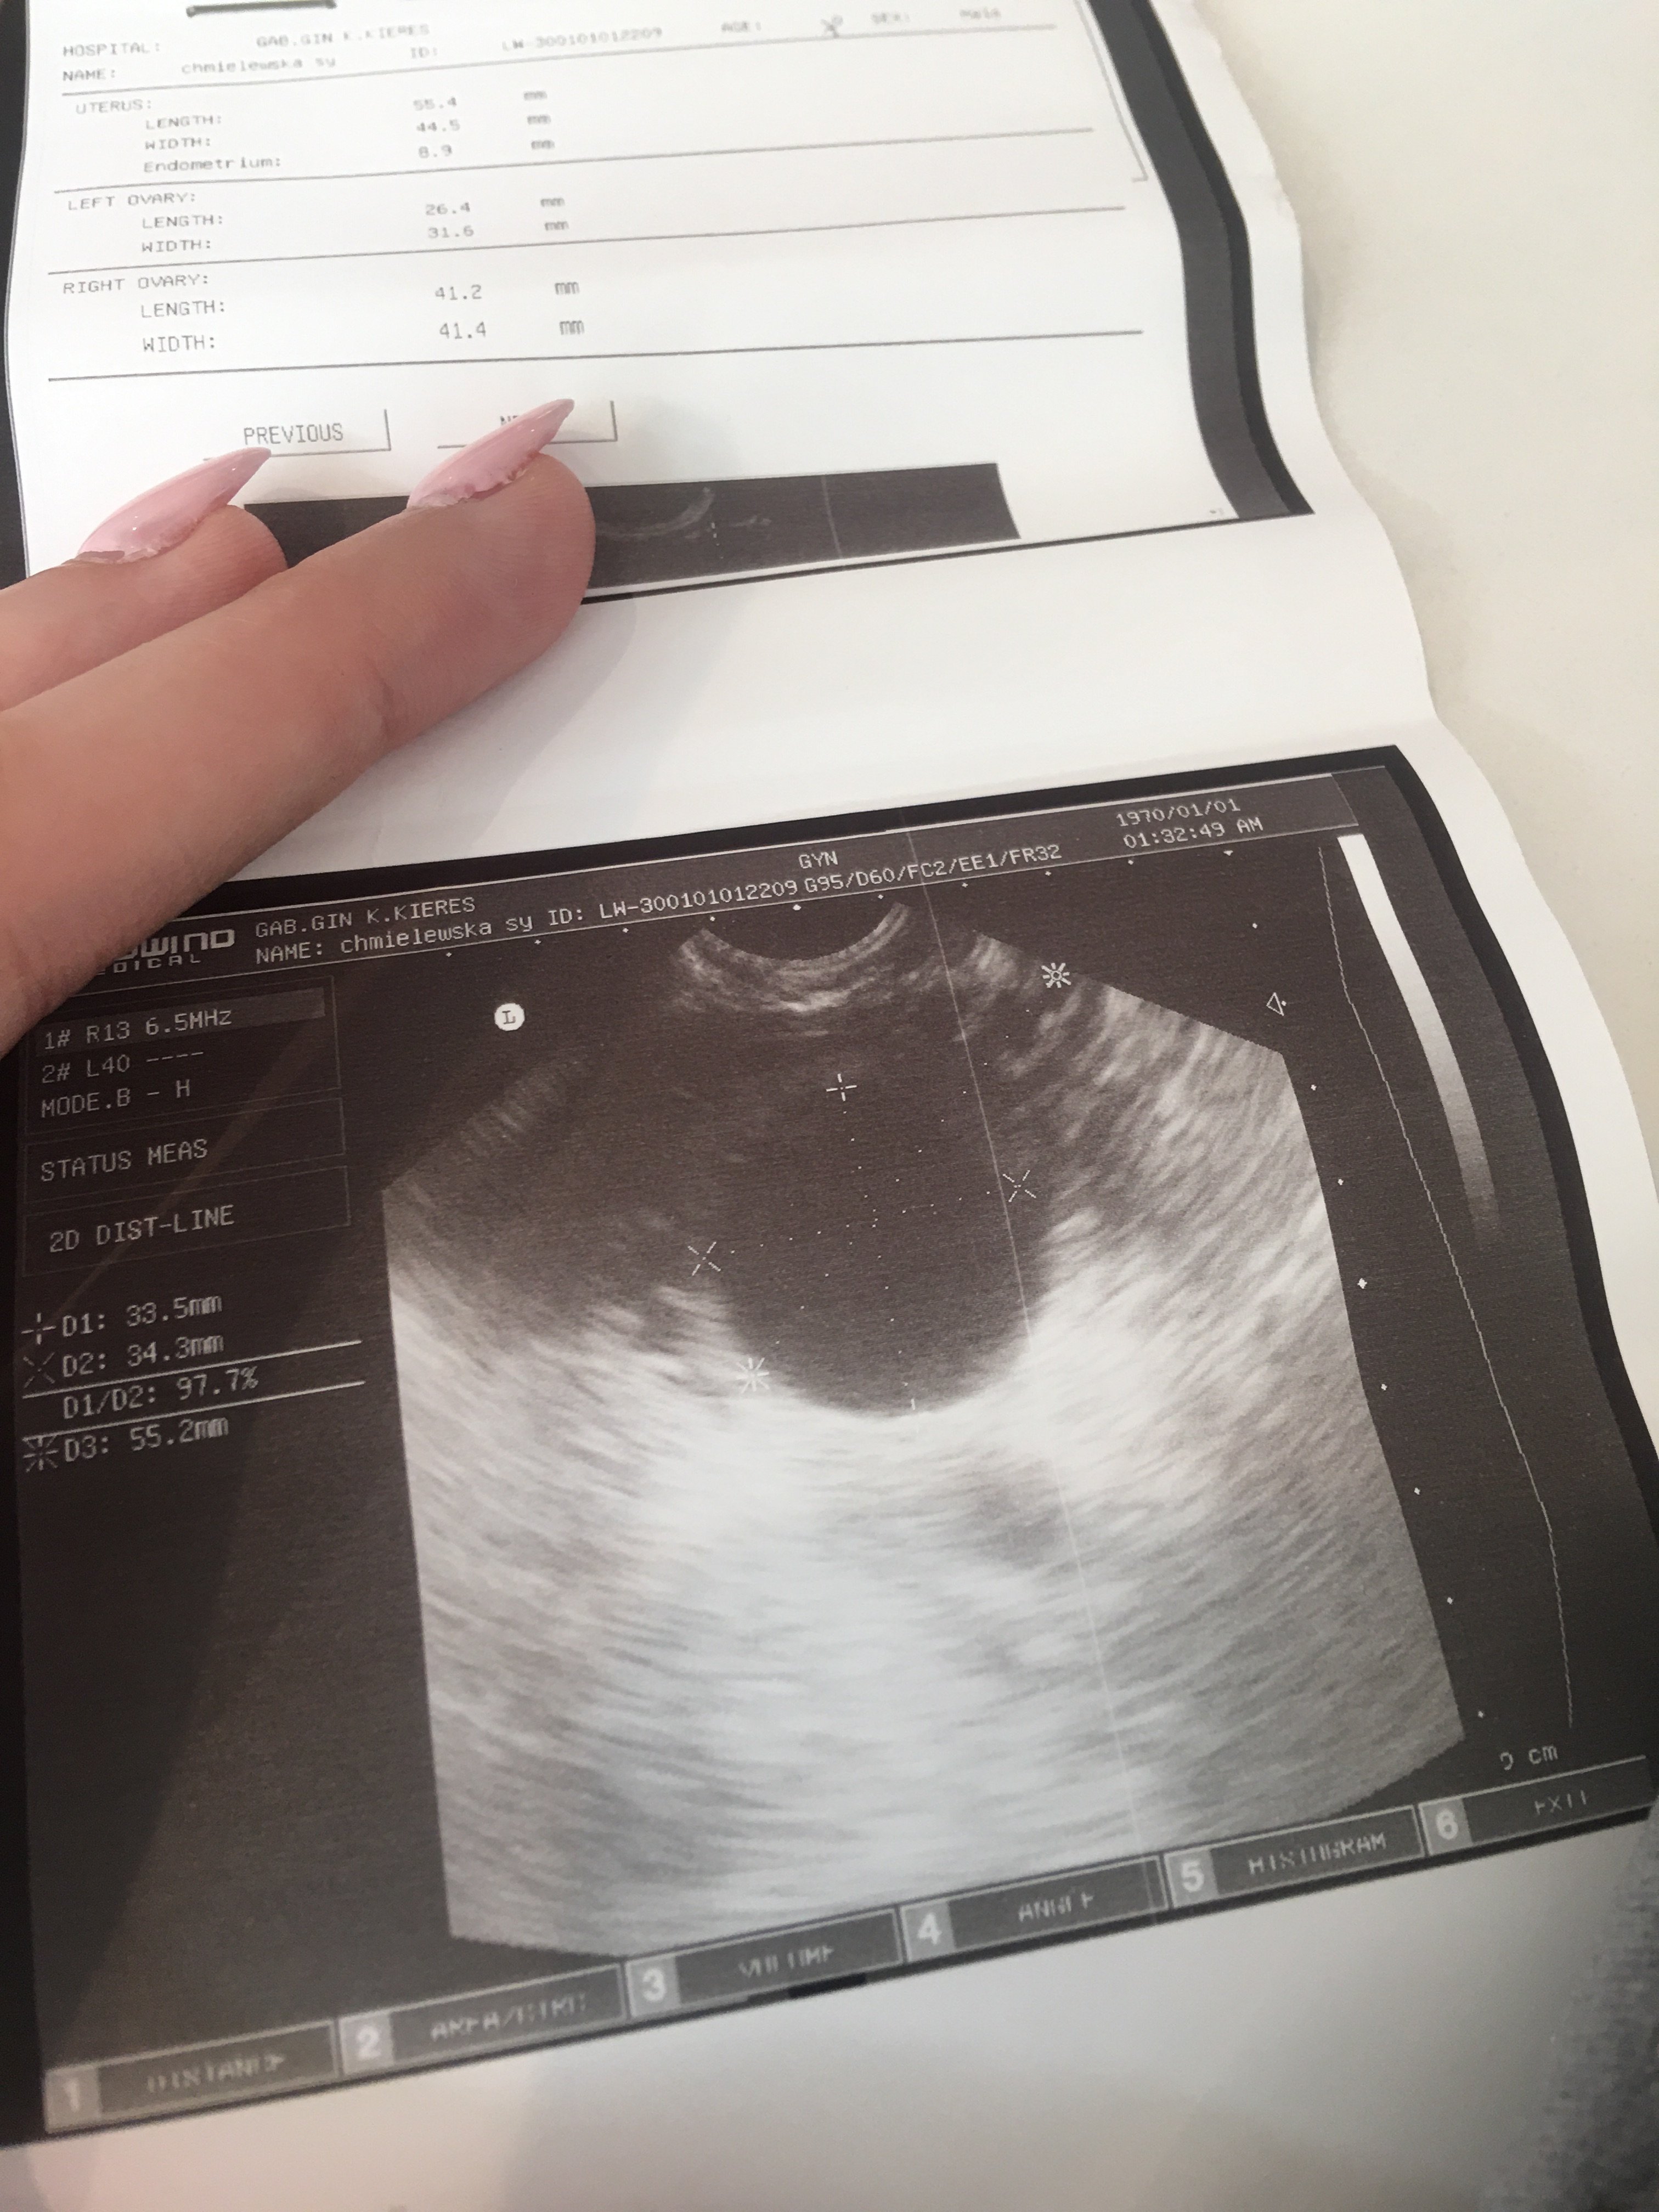

Hej dziewczyny wracam właśnie z wizyty u lekarza i jestem lekko załamana. Zrobił mi usg i mówi ze jestem w środku lekko spuchnięta i zaczerwieniona. Na usg wyszło jakieś coś i lekarka nie wie na ten czas czy to torbiel czy wrzesna ciąża i pęcherzyk. Mam lekkie bóle podbrzusza i parcie na przecherz i z tych nerwów słabo mi się robi. Mam pocZekac tydzień iść

Na betę i wrócić z wynikami. Ale dziwne bo byłam u niej miesiąc temu i na usg było czysto a tu nagle coś 33mm. Miała któraś z was tak bo ja wariuje

@Sylwia199630 O tym pisałam Ci wcześniej - że może być za wcześnie na pęcherzyk. To na USG wygląda jak jakaś torbiel. To jest zdecydowanie za duże na pęcherzyk ciążowy na tym etapie. Ale to jeszcze nic nie oznacza - postaraj się nie stresować i poczekać na wizytę. Powtórz betę, ale tak by mieć drugi wynik z pobrania po 48h.

Na betę i wrócić z wynikami. Ale dziwne bo byłam u niej miesiąc temu i na usg było czysto a tu nagle coś 33mm. Miała któraś z was tak bo ja wariuje Zobacz załącznik 1134710

Ja bym poszła na bete już dziś, nie wiem.co to jest zaznaczone ,ale to nie ciąza, ciąża to byłby tako malutki czarny punkcik